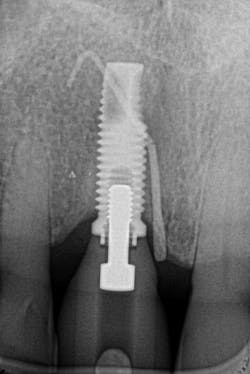

Figures 25 and 26: One-year postsurgery. Clinically all signs of retrograde peri-implantitis have been eliminated and radiographic bone fill can be seen.

The Er:YAG laser has been more recently known for its ability to remove calculus from a titanium implant surface as well as detoxification (figures 17–21).9 Many authors have shown the laser’s use in combination with mechanical debridement to be superior when using a regenerative approach to treat peri-implant diseases (figures 22–26).10 A particular feature of this laser is the microexplosions that occur when the laser energy is absorbed by water. The volume of these explosions suddenly expand up to 1,000 times, covering more surface area of a titanium implant. It has been found that both contaminated debris and the contaminated oxide layer are removed as a result of these microexplosions.11